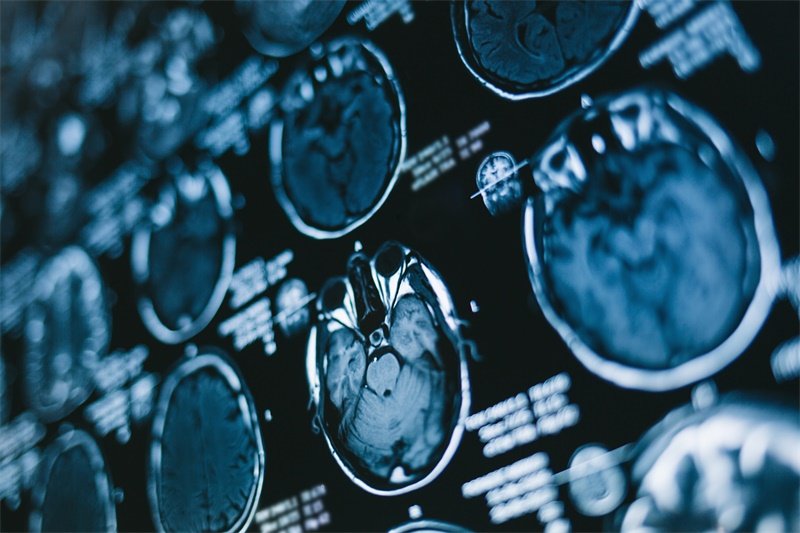

在临床上,对于这些占位性病变的诊断和治疗,通常需要通过影像学检查,如CT或MRI扫描,来明确其性质和范围。根据占位的性质,医生可能会制定相应的治疗方案。

针对侧脑室后角的占位,通常采用影像学检查来进行诊断。CT和MRI是最常用的两种影像学检查工具,可以详细展示脑部的结构变化。

计算机断层扫描(CT)具有快速和直观的优点,可以帮助医生迅速了解脑内是否存在占位性病变。

MRI扫描

磁共振成像(MRI)则提供了更为清晰的图像,能够帮助医生准确评估占位的性质和影响,尤其是在软组织的显示方面更具优势。

在某些情况下,医生还可能会推荐进行穿刺活检,以获取组织样本,进一步确定占位病变的性质。